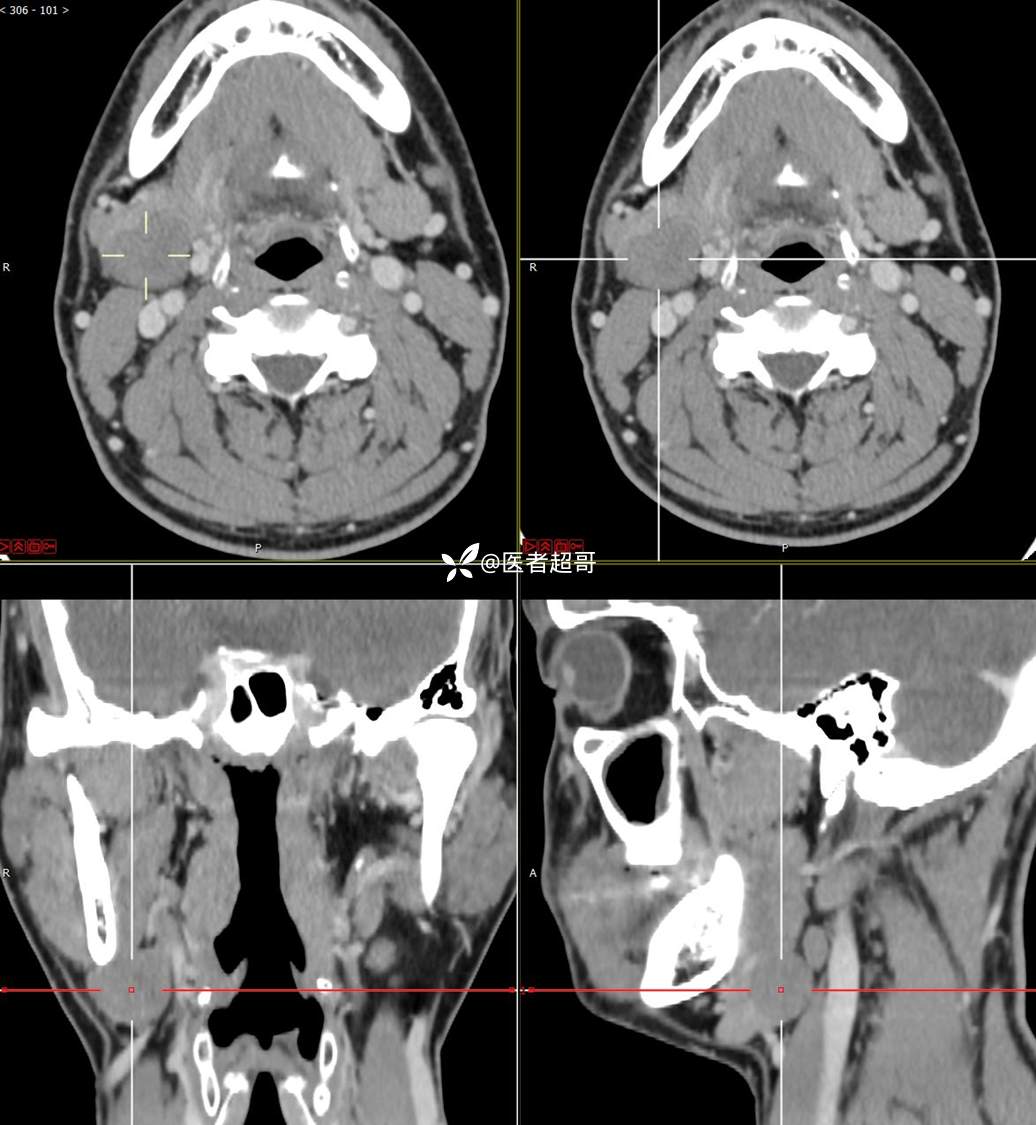

颌下腺结节:青年男性,颌下区无痛性肿物,请分析~~~

主 诉:发现右颌下区无痛性肿物1年。

现病史:患者于1年前发现右颌下区一肿物,肿物约“葡萄粒”大小,无疼痛不适,无进食时颌下区肿胀及疼痛不适。2023-10-1就诊于市中医院行超声检查;未予治疗。肿物体积无明显变化,求进一步治疗就诊于我院门诊,门诊以“颌下肿物”收入我科。患者自发病以来,神志清,精神佳,食欲好,睡眠好,大小便正常,近期体重无明显变化。